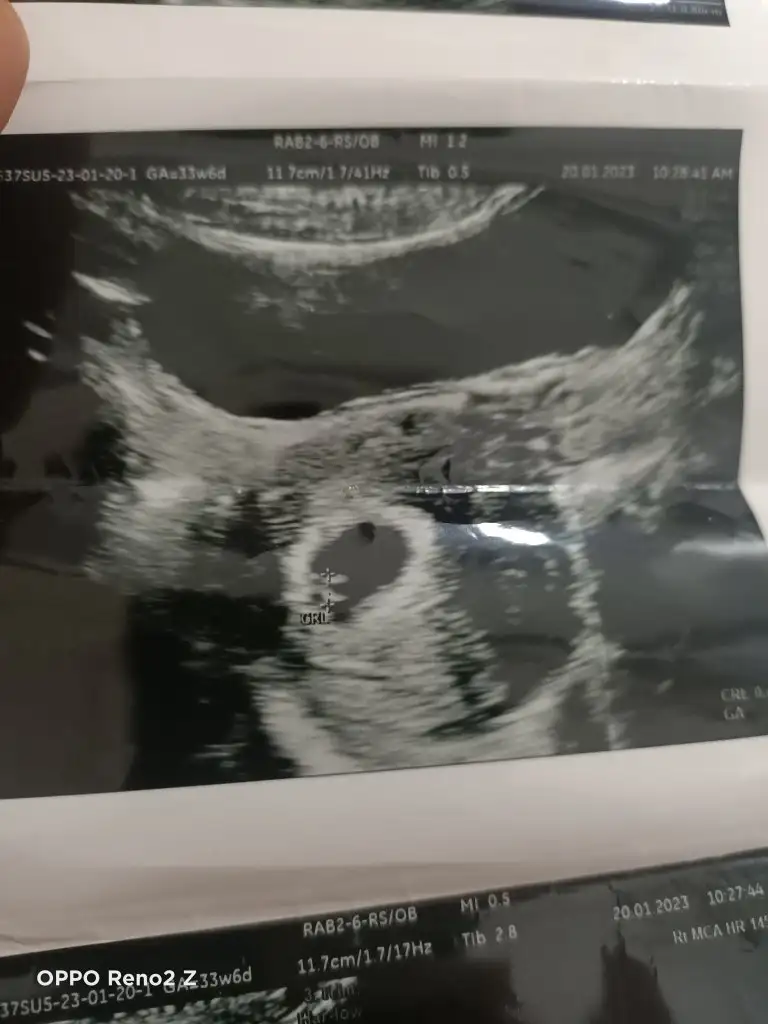

Nub ramzi tahmin edeyim kızlar

Kızlar ultrason fotolarınızı atın 6 ve 7.hafta ya da 11. 12. 13. Hafta yorumlayayim. Amacım kesin bilmek değil net bi şey söyleyemem ancak ultrason net olursa daha iyi olur :)

Karından canım ama ikizlik şüphesi var sence ikiz de olabilir mi yoksa birisi yolk kesesimi doktorum net birşey söylemedi🥰❤️

Canım plasentanın parlak tarafı assa doğru duruyor asla anlamadım bebegn konumuna göre plasentanın sola daha yakın oldgnu düşünürsek erkek dye tahmin yuruteblrm canim.